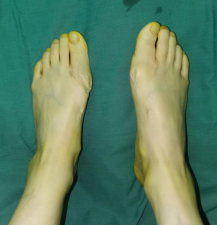

术前外观

术后即刻外观